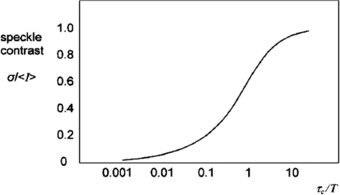

If there are moving scatterers associated with the illuminated surface (moving erythrocytes, for example), the speckles will become de-correlated over time and the contrast will vary. Integrating K over a short exposure time T (typically 20 ms) and across a small surface area (typically 5 × 5 pixels) allows an estimate of the speckle correlation time τc which will in turn be proportional to the velocity of the scatterers.

Figure 6 shows a theoretical plot of image contrast K against the ratio of correlation time to exposure time for a Lorentzian velocity distribution, whereby it is assumed the mean velocity is zero with an equal likelihood of positive and negative velocities. This would be a reasonable model to represent the random architecture of the microvasculature. Figure 6 also demonstrates how integration time T can be adjusted to select an appropriate range of erythrocyte velocities. It is necessary to operate along the steepest part of the curve to achieve the greatest sensitivity to change in perfusion.

Figure 6. Speckle contrast (K) versus the ratio of speckle correlation time to exposure for Lorentzian flow (reproduced with permission from Briers 2001 Physiol. Meas. 22 R35–66).